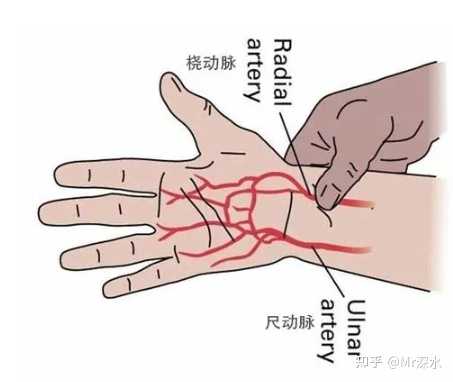

�����������ľ������������ײ��������������������㱳�����ⲻ�����ֺ������㱳������ |